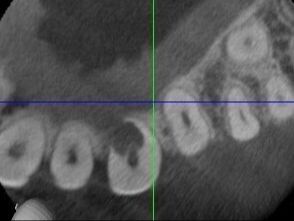

SURGICAL RESORPTION REPAIR

The Protocol for Treating External Root Resorption

In this free training, Dr. Simon will walk you through a clear and predictable protocol to treat external root resorption lesions as well as the diagnostic and decision-making process.

He will explain the step-by-step process including the materials he uses and the patient instructions he gives to ensure success.